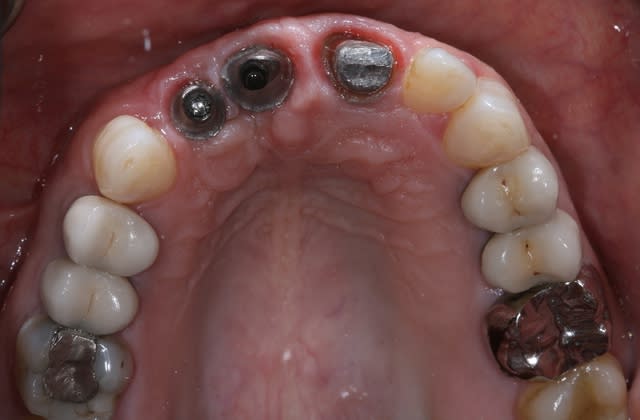

Patiente de 30 ans suite à parodontite a perdu 11-12 avec grosse perte osseuse.

J'ai suffisamment d'os pour prévoir la pose implantaire sans greffe mais esthétiquement je pense que cela va être moche car la ligne du sourire me semble bien haute.

Bon voila le scann de 11-12 (pas 21-22 comme noté)

C'est vrai que j'ai à mort d'os en épaisseur.

Le manque est surtout en hauteur.

Dans tous les cas je refais 21 en même temps.

Bon ben j'ai implanté avant d'avoir refait la 21. Du coup j'ai mésialé la pose de 11 pour compenser la distalisation de 21.

Au final je n'ai pas fait de greffe osseuse... et j'ai réalisé une technique de rouleau sur 11-12 mais je reste un peu court à mon goût.

J'ai mis en place des transitoires sur 11-12-21 pour temporiser 3 mois pour voir la maturation des tissus mous.